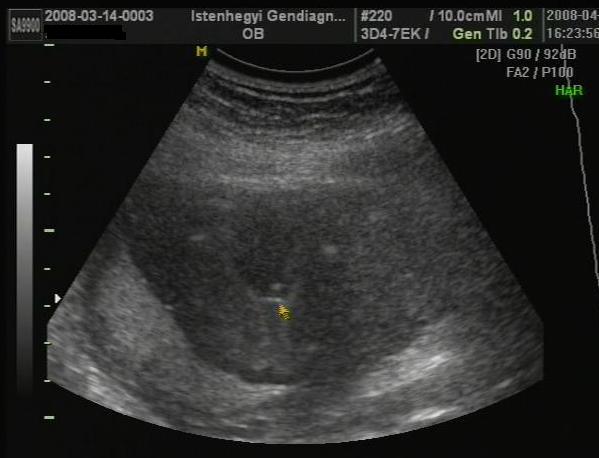

Voltunk ma uh-n. Minden rendben van, baba korának megfelelő, megvan mindene, 235 g és FIÚ!!!!!!! :lol: :lol: :lol: :lol: